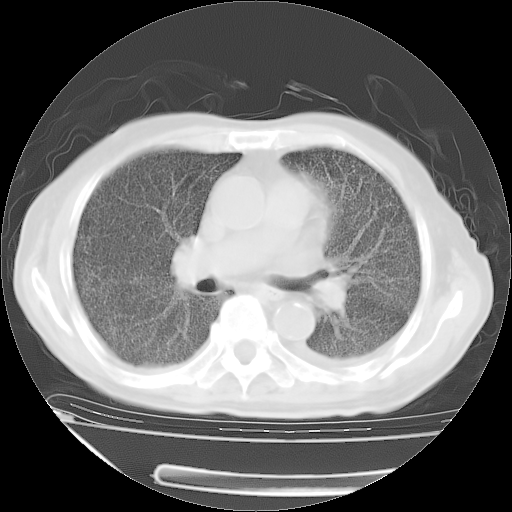

甲强龙80mg/日+抗结核治疗(异烟肼+利福霉素+乙胺丁醇)10天。复查肺部CT。

治疗10天肺部CT